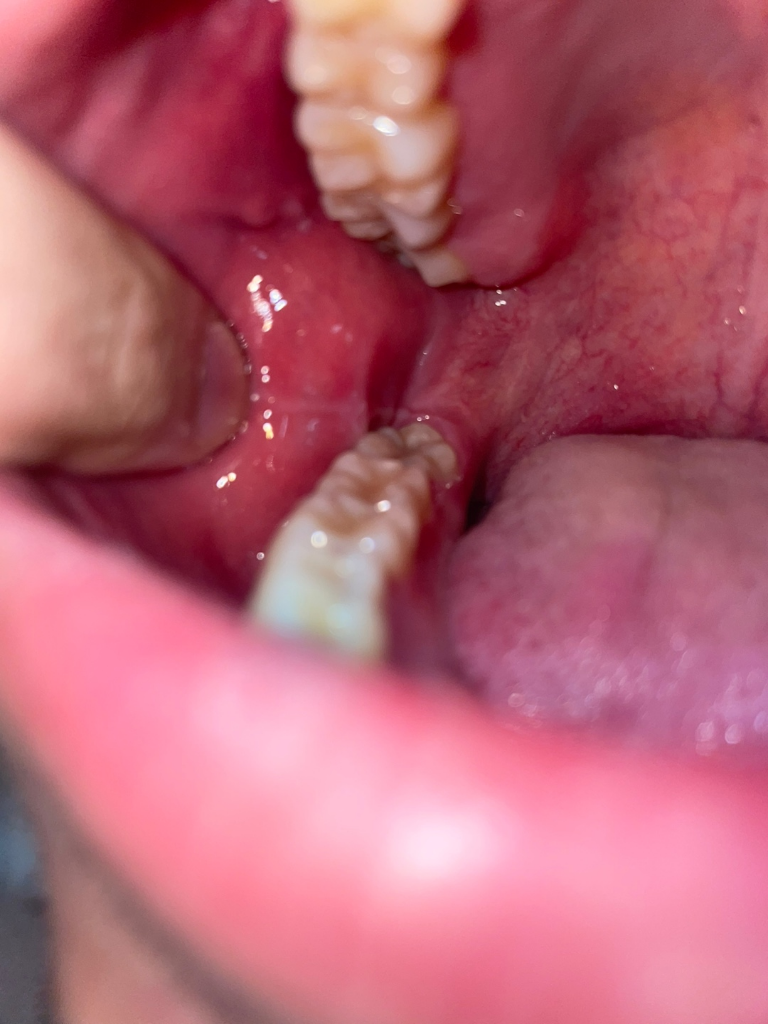

양쪽 어금니 쪽 볼에 혹?처럼 뭐가 생겼어요 깨문기억은 없는데 혹시 구강암이런것과 관련있나요?

한 3일전쯤까진 없었는데 그쯤 양쪽 어금니 쪽에 볼에 혹? 염증? 같은 그런게 생겼어요

그리고 사진에 보면 어금니 뒤쪽 흰색부분이 있는데 이건 왜 그럴까요 이건 언제부터 생긴건지는 모르겠습니다. 잘 안보이실까 하여 표시안한 원본사진도 첨부합니다

해당부위는 볼의 연조직이 치아 사이에 밀려 들어가면서 생기는 증상으로 보입니다.

구강암이 아니고 볼이 치아에 씹혀서 생긴겁니다. 문제가 잇는건 아니니 너무 걱정하지마세요.

사진상으로는 씹어서 생긴 외상성 궤양이 맞습니다

특별히 치아에 보철치료나 충치치료를 하고 생긴 변화가 아니기 때문에 치과적으로 처치를 해줄 건 없고 외상성 궤양도 시간이 지나면 자연스럽게 회복됩니다. 좀 더 빠른 회복을 위해서는 구강 내에 적용하는 연고를 바르셔도 좋습니다.